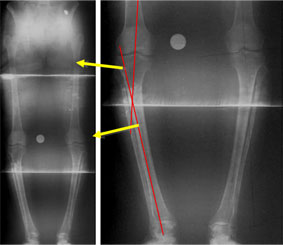

In the example shown here, the patient had a varus deformity of both tibiae (bow legs – reduced angle at the bone below the knee) with slight external rotation deformity of the tibiae (the feet pointing outward while the patellae [knee caps] face forward).

The deformities were corrected on both the sides acutely (at one go during surgery) and LRS (Limb Reconstruction System) fixator was applied on each side. |

The full length x-ray shows the seat of deformity as the upper tibial diaphysis (shaft). Femur on both the sides is normal.

A rotational profile CT scan is also done to find out the relationships of femoral neck axis, distal femoral condylar axis, proximal tibial axis and the intermalleolar axis. This helps in identifying any rotational deformity. |